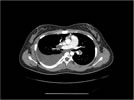

We ordered a CT scan with infusion of the chest

I will show you 12 CT-scan cuts.